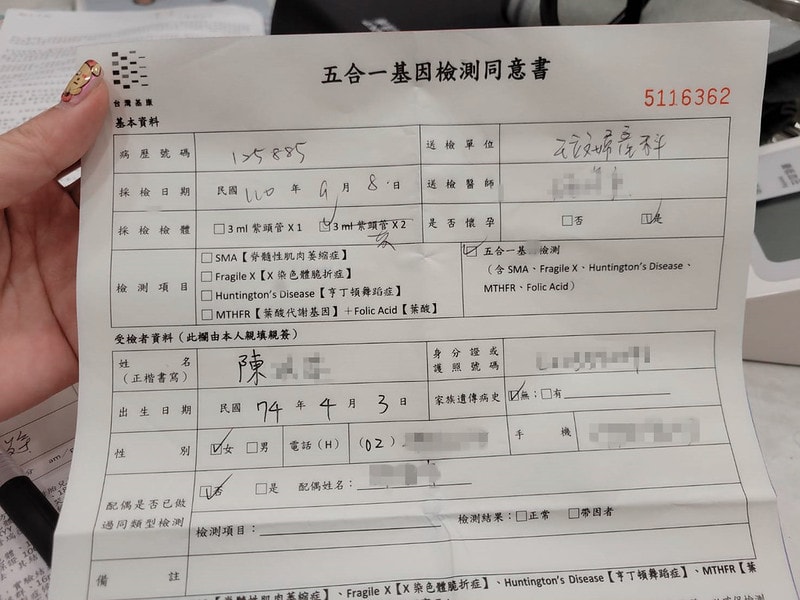

然後就是要填一堆表格

五合一基因檢測只有第一次懷孕要做

脊髓性肌肉萎縮症

X染色體脆折症

亨丁頓舞蹈症

葉酸代謝基因跟葉酸

之後如果要生二胎或是三胎就不用了

費用大概是5500左右

這部分的檢查

我後來是都沒有問題

葉酸也算偏高